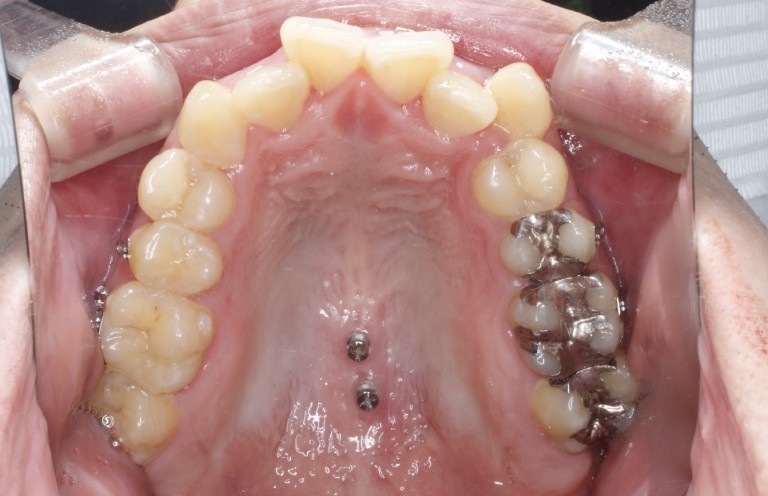

安心・安全歯科矯正用アンカースクリューこの症例にこの方法 安心・安全 歯科矯正用アンカースクリュー この症例にこの方法/医歯薬

「安心・安全歯科矯正用アンカースクリューこの症例にこの方法」定価: ¥ 22000購入して一度も読んでません。本棚に保管してました。細かいスレ等あると思いますので、ご理解いただける方のみ購入お願いいたします。#本 #自然/医療・薬学・健康